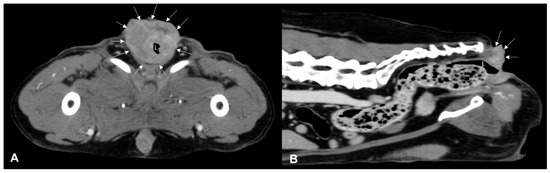

CT identified a colorectal lesion in all dogs. Specifically, 5 dogs had lesions localized at the colorectal junction, 3 at the descending colon, 1 at the transverse colon, and 1 at the anorectal junction. The characteristics of these lesions varied: 6 (Figure 1) dogs exhibited transmural, circumferential, asymmetric thickening of the wall, while 2 (Figure 2) cases (one adenocarcinoma and one carcinoma) displayed transmural, circumferential symmetric thickening. The leiomyosarcoma case was characterized by the presence of an exophytic mass (Figure 3).

Luminal stenosis was noted in all cases except for two: the descending colic leiomyosarcoma and the colorectal adenocarcinoma. In one case of anorectal squamous cell carcinoma, the infiltration of surrounding structures such as anal sacs and tail muscles was observed. Additionally, adherences between the lesion and surrounding structures like the urinary bladder, sacro-caudal muscles and epaxial muscles, tail of the spleen, and/or left external iliac artery were noted in 4, 3, and 1 dog, respectively.

Figure 2. Post-contrast CT images of an anorectal squamous carcinoma in a 15-year-old neutered male Epagneul Breton. Transverse (A) and sagittal (B) plane reconstructions are available. A transmural, circumferential, asymmetric, heterogeneously enhancing expansile lesion is observed (white arrows). On the sagittal plane, the lesion exhibits a mild exophytic appearance and encircles the anal sac and borders, effacing any adipose cleavage with the tail muscles. L—lumen.